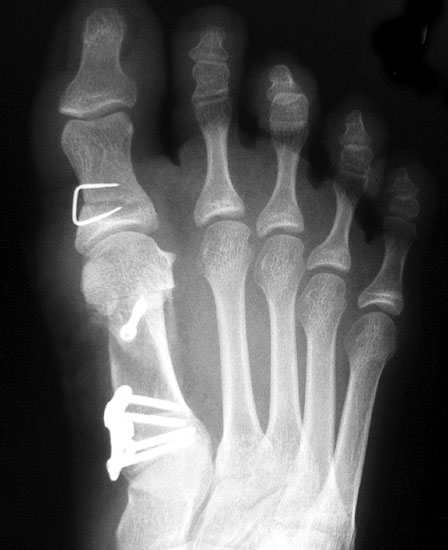

Beim Follow up nach 6 Monaten zeigte sich eine Korrektur des ersten Intermetatarsalwinkels (IMW) um durchschnittlich 9° (Range 4-15°) auf Normwerte (6,8° SD 1,3) (Abb. 21).

Gutes postoperatives Ergebnis mit physiologischem Intermetatarsale I-II Winkel nach open wedge Osteotomie.

Abbildung 21

In zwei Fällen kam es intraoperativ zu einem Bruch der lateralen Kortikalis. In einem Fall konnte durch die winkelstabile Platte eine ausreichende Stabilität erzielt werden, in dem anderen Fall wurde zusätzlich ein perkutaner Kirschnerdraht eingebracht, der nach 6 Wochen entfernt wurde. Eine stabile knöcherne Konsolidierung der Osteotomie ohne Korrekturverlust konnte in beiden Fällen erreicht werden. Die Analyse der Röntgenaufnahmen ergab eine Verlängerung des Os metatarsale I von durchschnittlich 1,8 mm (Range 1-4 mm).